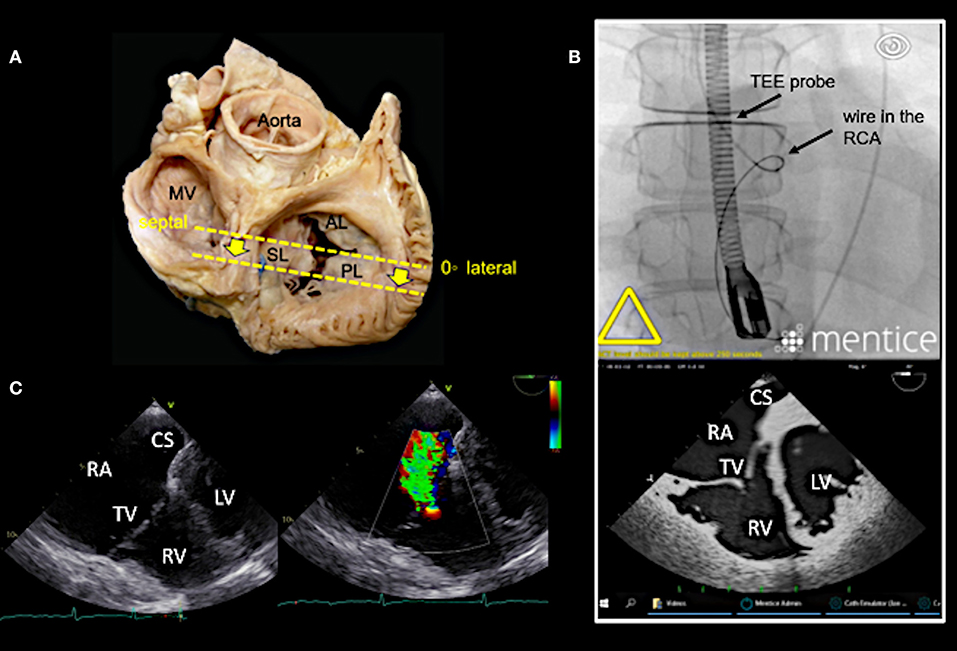

Figure 3. Main transesophageal echocardiographic (TEE) imaging planes for the assessment of the tricuspid valve (TV): the mid- esophageal 4-chamber view (0–10°). (A) The main imaging planes for assessing a TV using TEE are shown in an anatomical image of a TV with 3 leaflets. (B) The specific imaging plane for the mid-esophageal 4-chamber view is shown. (C) By using commercial simulation software (Mentice Healthy Simulation; version VIST G5; Gothenburg, Sweden) TEE and fluoroscopic views can be generated simultaneously based on MDCT data sets. The upper picture shows the necessary positioning of the TEE probe in fluoroscopy (35° RAO, 6° CRANIAL) to create a mid-esophageal 4-chamber view at 0° (see image below). (D) A standard 2D TEE view at 0° is shown. RA, right atrium; RV, right ventricle; RAA, right atrial appendage; RCA, right coronary artery; LA, left atrium; LV, left ventricle; MV, mitral valve; SL, septal leaflet; AL, anterior leaflet; PL, posterior leaflet; MDCT, multi-detector computed tomography; Abbreviations are also used for Figures 4–7.

Figure 4. Deep esophageal view at 0–10°. (A) The specific imaging plane for the deep esophageal view is shown (see also Figure 3A). Starting from the mid-esophageal 4-chamber view at 0–10°, the probe is advanced deeper until the CS becomes visible. This maneuver allows for an easy evaluation of the septal leaflet. The evaluation of the posterior region of the septal and the posterior leaflets is of particular importance since the main axis of tricuspid annular dilation is in anterior-posterior direction and leaflet retraction is often pronounced in the posterior part. (B) The upper picture shows the necessary positioning of the TEE probe in fluoroscopy (35° RAO, 6° CRANIAL) to create the deep esophageal view at 0° (see image below). (C) The corresponding 2D TEE view without (left) and with (right) color Doppler is shown. CS, coronary sinus; other abbreviations see Figure 3.